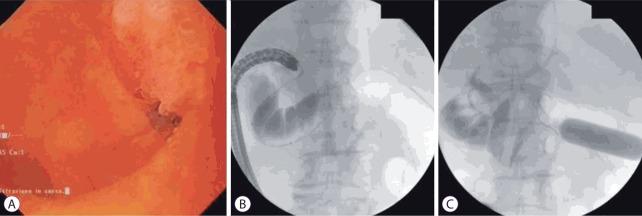

De-novo Gastrointestinal Anastomosis with Lumen Apposing Metal Stent.

Gastric outlet obstruction, afferent or efferent limb obstruction, and biliary obstruction among patients with altered anatomy often require surgical intervention which is associated with significant morbidity and mortality. Endoscopic dilation for benign etiologies requires multiple sessions, whereas self-expandable metal stents used for malignant etiologies often fail due to tumor in-growth. Lumen apposing metal stents, placed endoscopically with the intent of creating a de-novo gastrointestinal anastomosis bypassing the site of obstruction, can potentially achieve similar efficacy, with a much lower complication rate. In our study cohort (n=79), the composite technical success rate and clinical success rate was 91.1% (72/79) and 97.2% (70/72), respectively. Five different techniques were used: 43% (34/79) underwent the balloon-assisted method, 27.9% (22/79) underwent endoscopic ultrasound-guided balloon occluded gastro-jejunostomy bypass, 20.3% (16/79) underwent the direct technique, 6.3% (5/79) underwent the hybrid rendezvous technique, and 2.5% (2/79) underwent natural orifice transluminal endoscopic surgery (NOTES)-assisted procedure. All techniques required an echoendoscope except NOTES. In all, 53.2% (42/79) had non-cautery enhanced Axios stent, 44.3% (35/79) had hot Axios stent, and 2.5% (2/79) had Niti-S spaxus stent. Symptom-recurrence was seen in 2.8%, and 6.3% had a complication (bleeding, abdominal pain or peritonitis). All procedures were performed by experts at centers of excellence with adequate surgical back up.